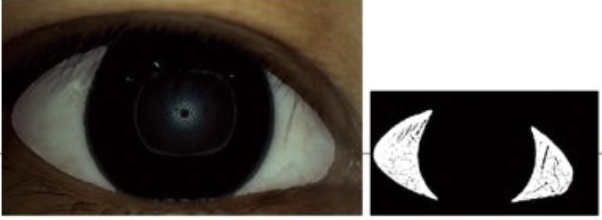

Cornea Sodium Fluorescein Staining

A special dye is used to detect damage or dry spots on the corneal surface. The dye highlights areas where the eye surface may be irritated or damaged due to insufficient lubrication.

Conjunctival Redness Analysis

This test measures the degree of redness and inflammation on the eye surface, helping doctors assess ocular surface health.